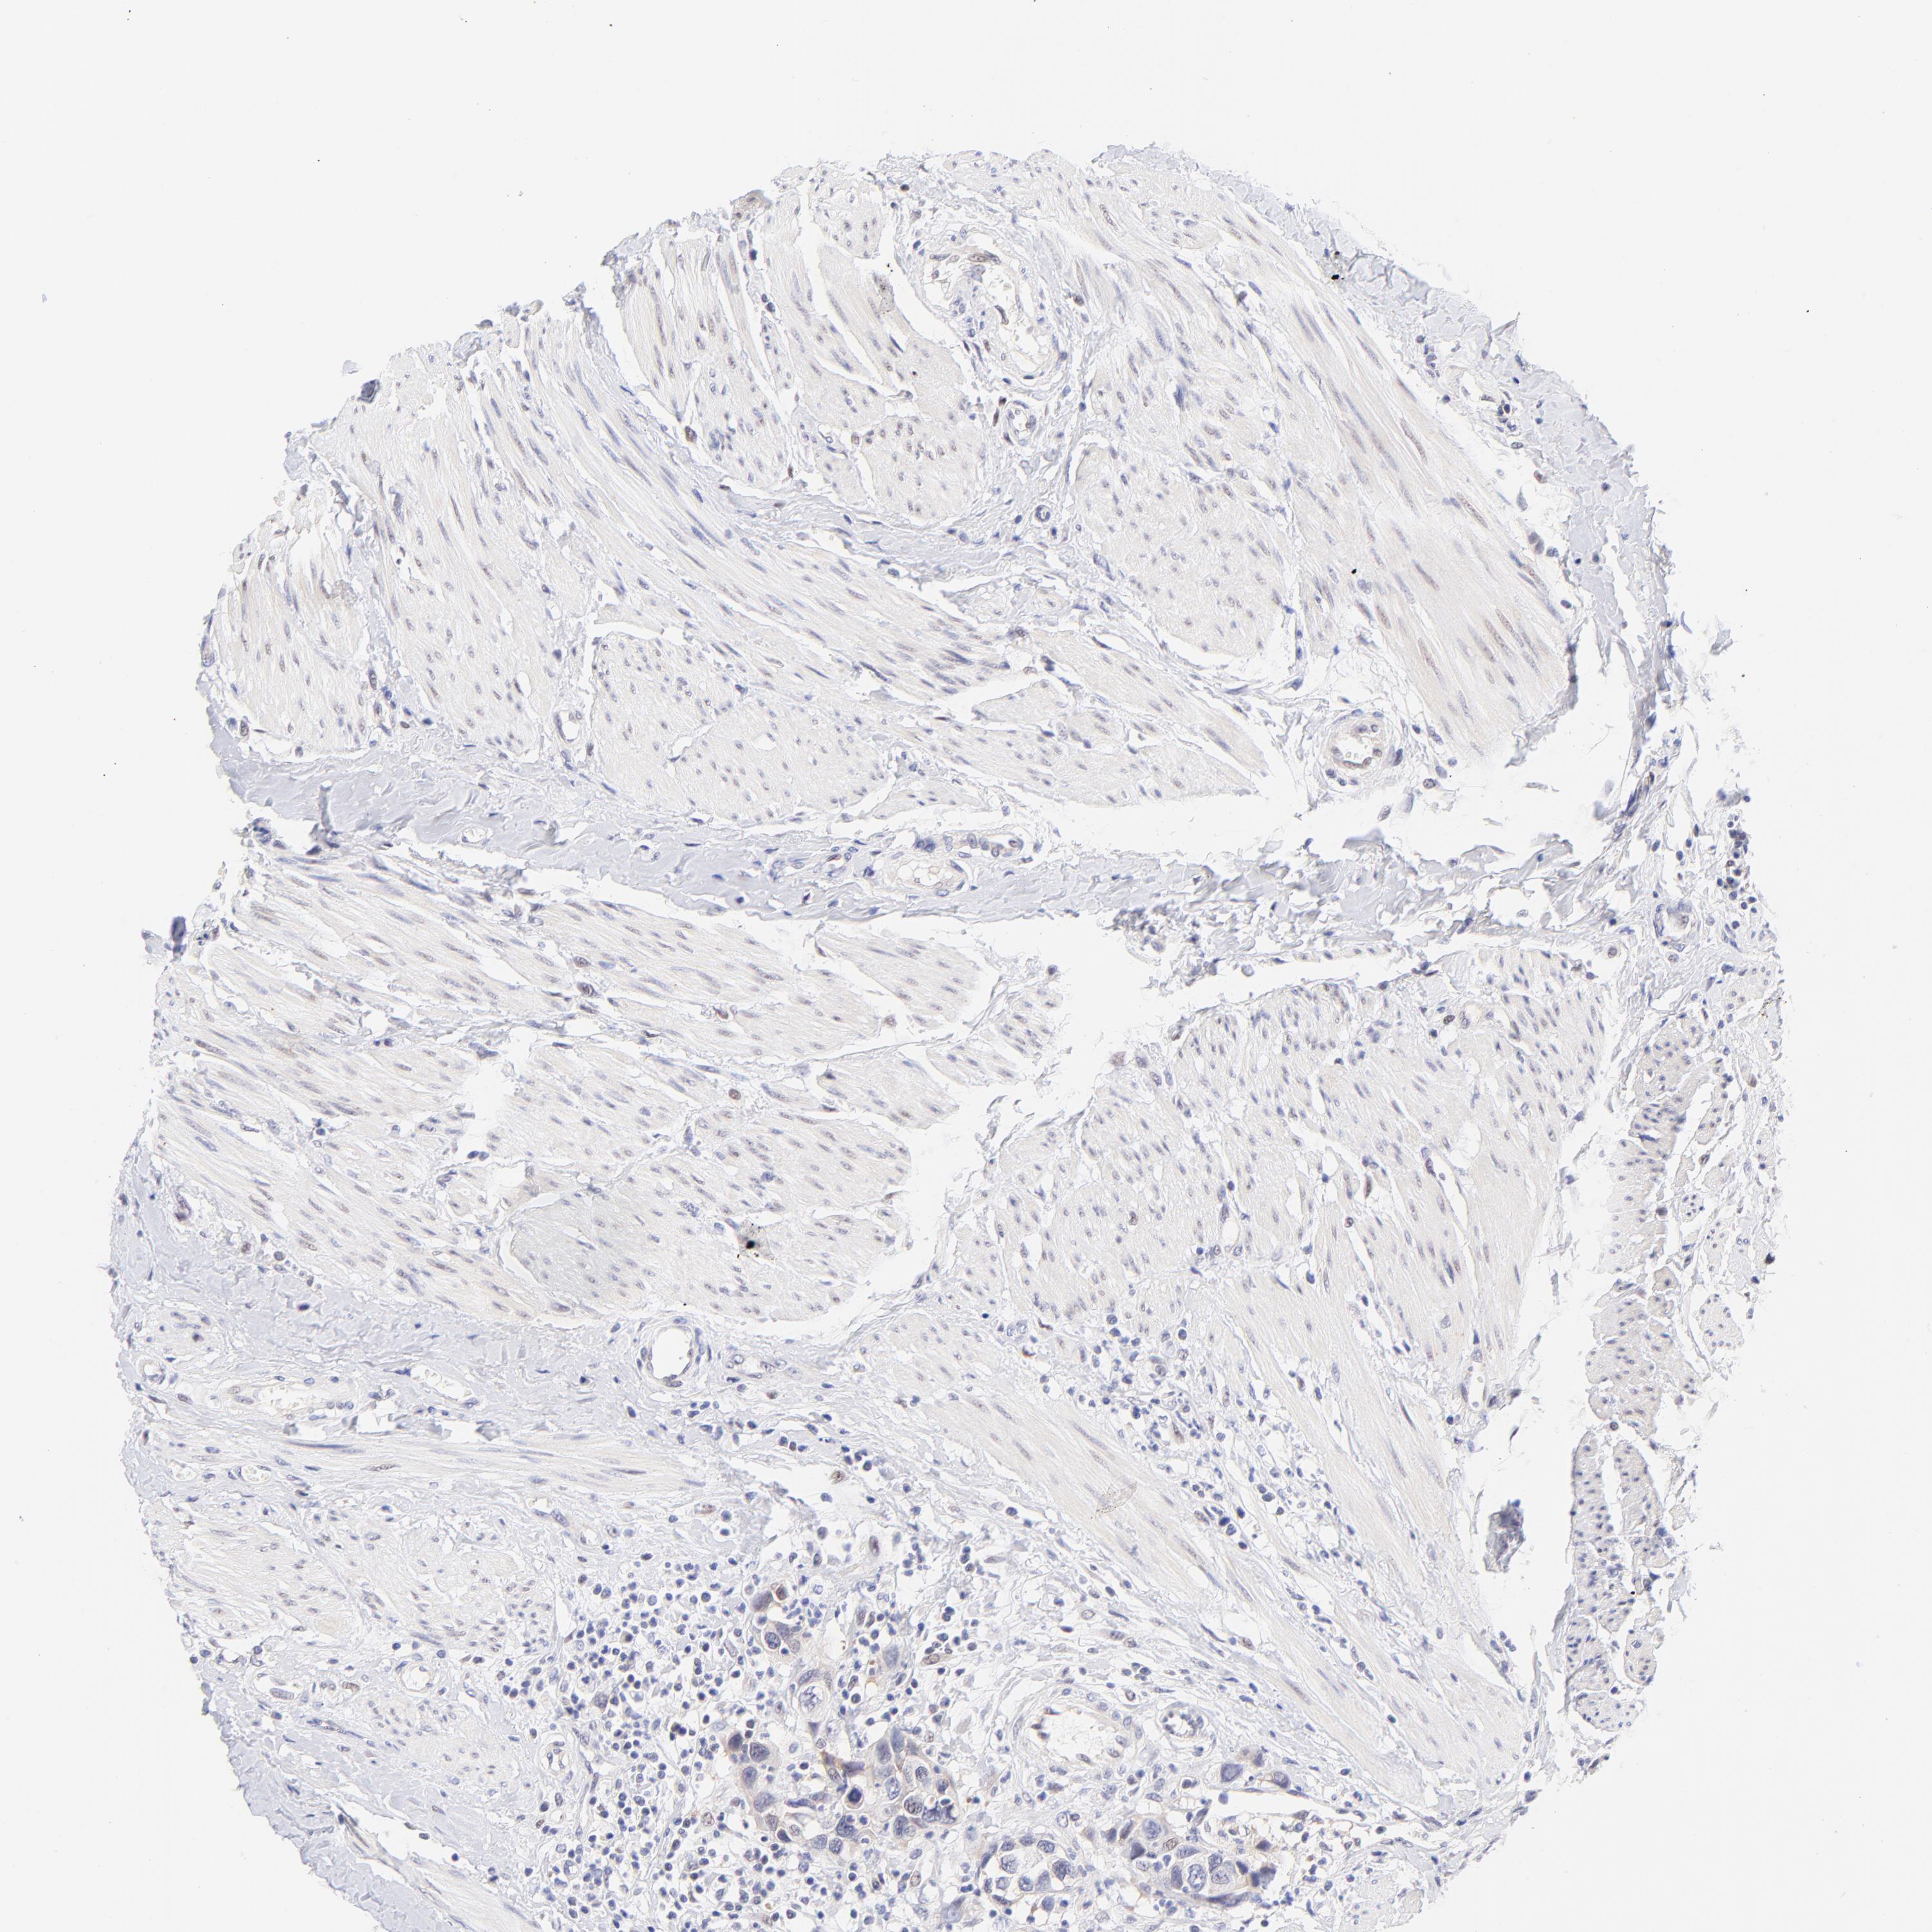

UROTHELIAL CANCER - Protein expressioni

A mouse-over function shows sample information and annotation data. Click on an image to view it in a full screen mode. Samples can be filtered based on level of antibody staining by selecting one or several of the following categories: high, medium, low and not detected. The assay and annotation is described here.

Antibody stainingi

Antibody staining in the annotated cell types in the current human tissue is reported as not detected, low, medium, or high, based on conventional immunohistochemistry profiling in selected tissues. This score is based on the combination of the staining intensity and fraction of stained cells.

Each image is clickable and will lead to virtual microscopy that enables deeper exploration of all samples and also displays staining intensity scores, fraction scores and subcellular localization as well as patient and tissue information for each sample.

Antibody HPA003155

Staining

High

Medium

Low

Not detected

Intensity

Strong

Moderate

Weak

Negative

Quantity

>75%

75%-25%

<25%

None

Location

Nuclear

Cytoplasmic/membranous

Cytoplasmic/membranous,nuclear

Urothelial carcinoma, High grade